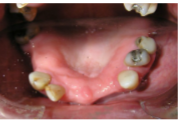

3. Presence of teeth

-UR7--- UR3UR2---UL3UL4UL5----

-LR7LR6--LR3LR2LR1LL1LL2LL3LL4--LR6--